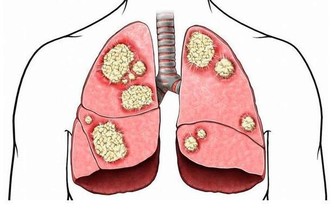

如:高血壓、哮喘、脂肪肝、心腦血管等疾。